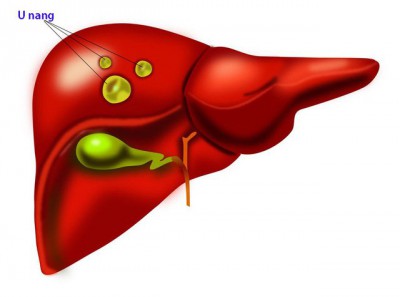

Khối u và u nang khác nhau thế nào?

U nang và khối u là hai loại u phổ biến. Rất khó để phân biệt chúng vì chúng thường được tìm thấy ở cùng một nơi. Ví dụ, có thể có cả u nang buồng trứng và khối u...